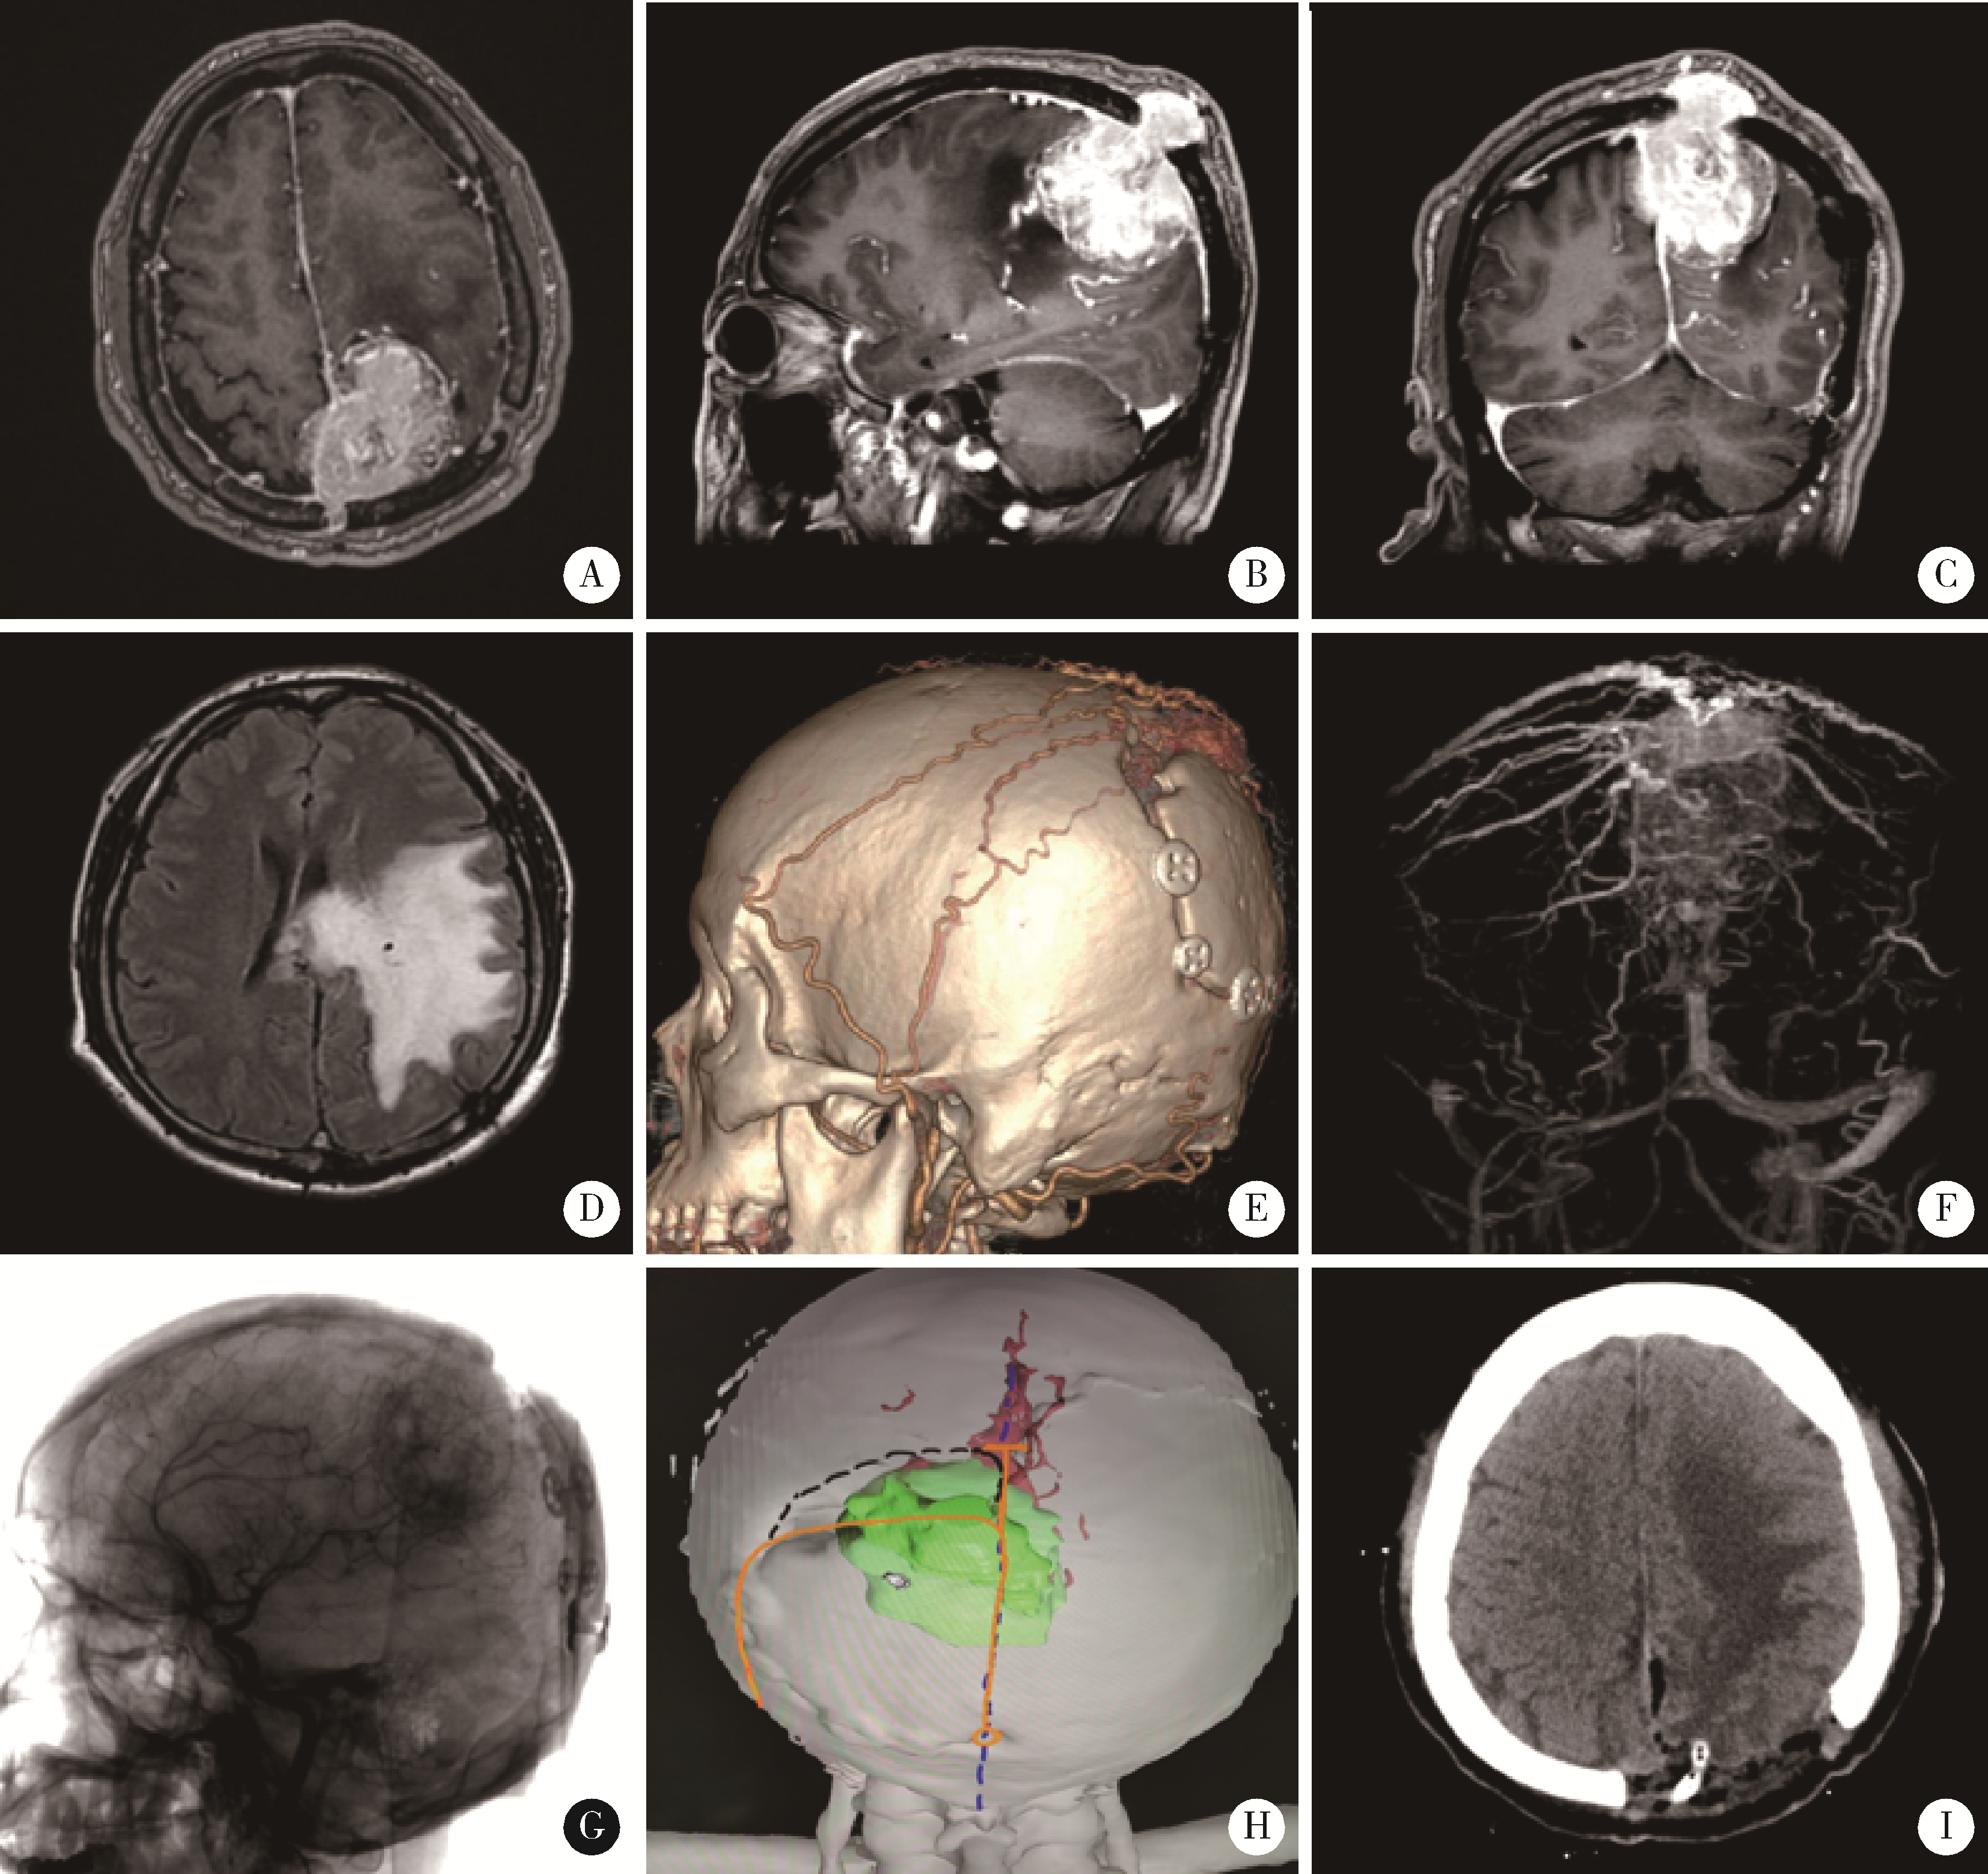

图1

男,56岁,左侧顶部上矢状窦旁复发脑膜瘤"